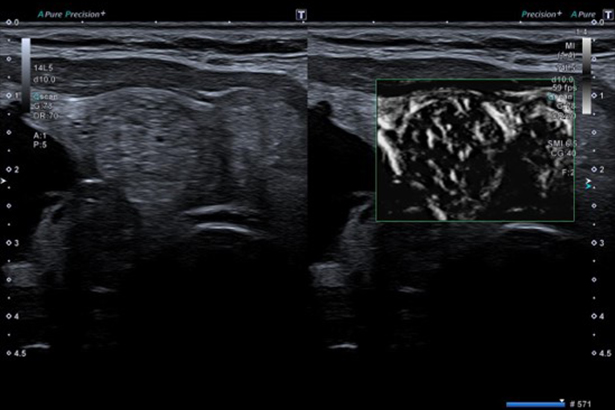

高達 18MHz 的高頻探頭群,可應用于肌肉、肌腱和神經的診斷。輕量、易握的曲棍球桿型探頭,適用于小關節、神經和術中的成像。肌骨探頭均支持 SMI 超微血流成像,高清敏感顯示微細血流。

SMI 擁有優異的低速血流成像能力,且具有高幀頻,在評估占位,囊腫和腫瘤時增強診斷信心。